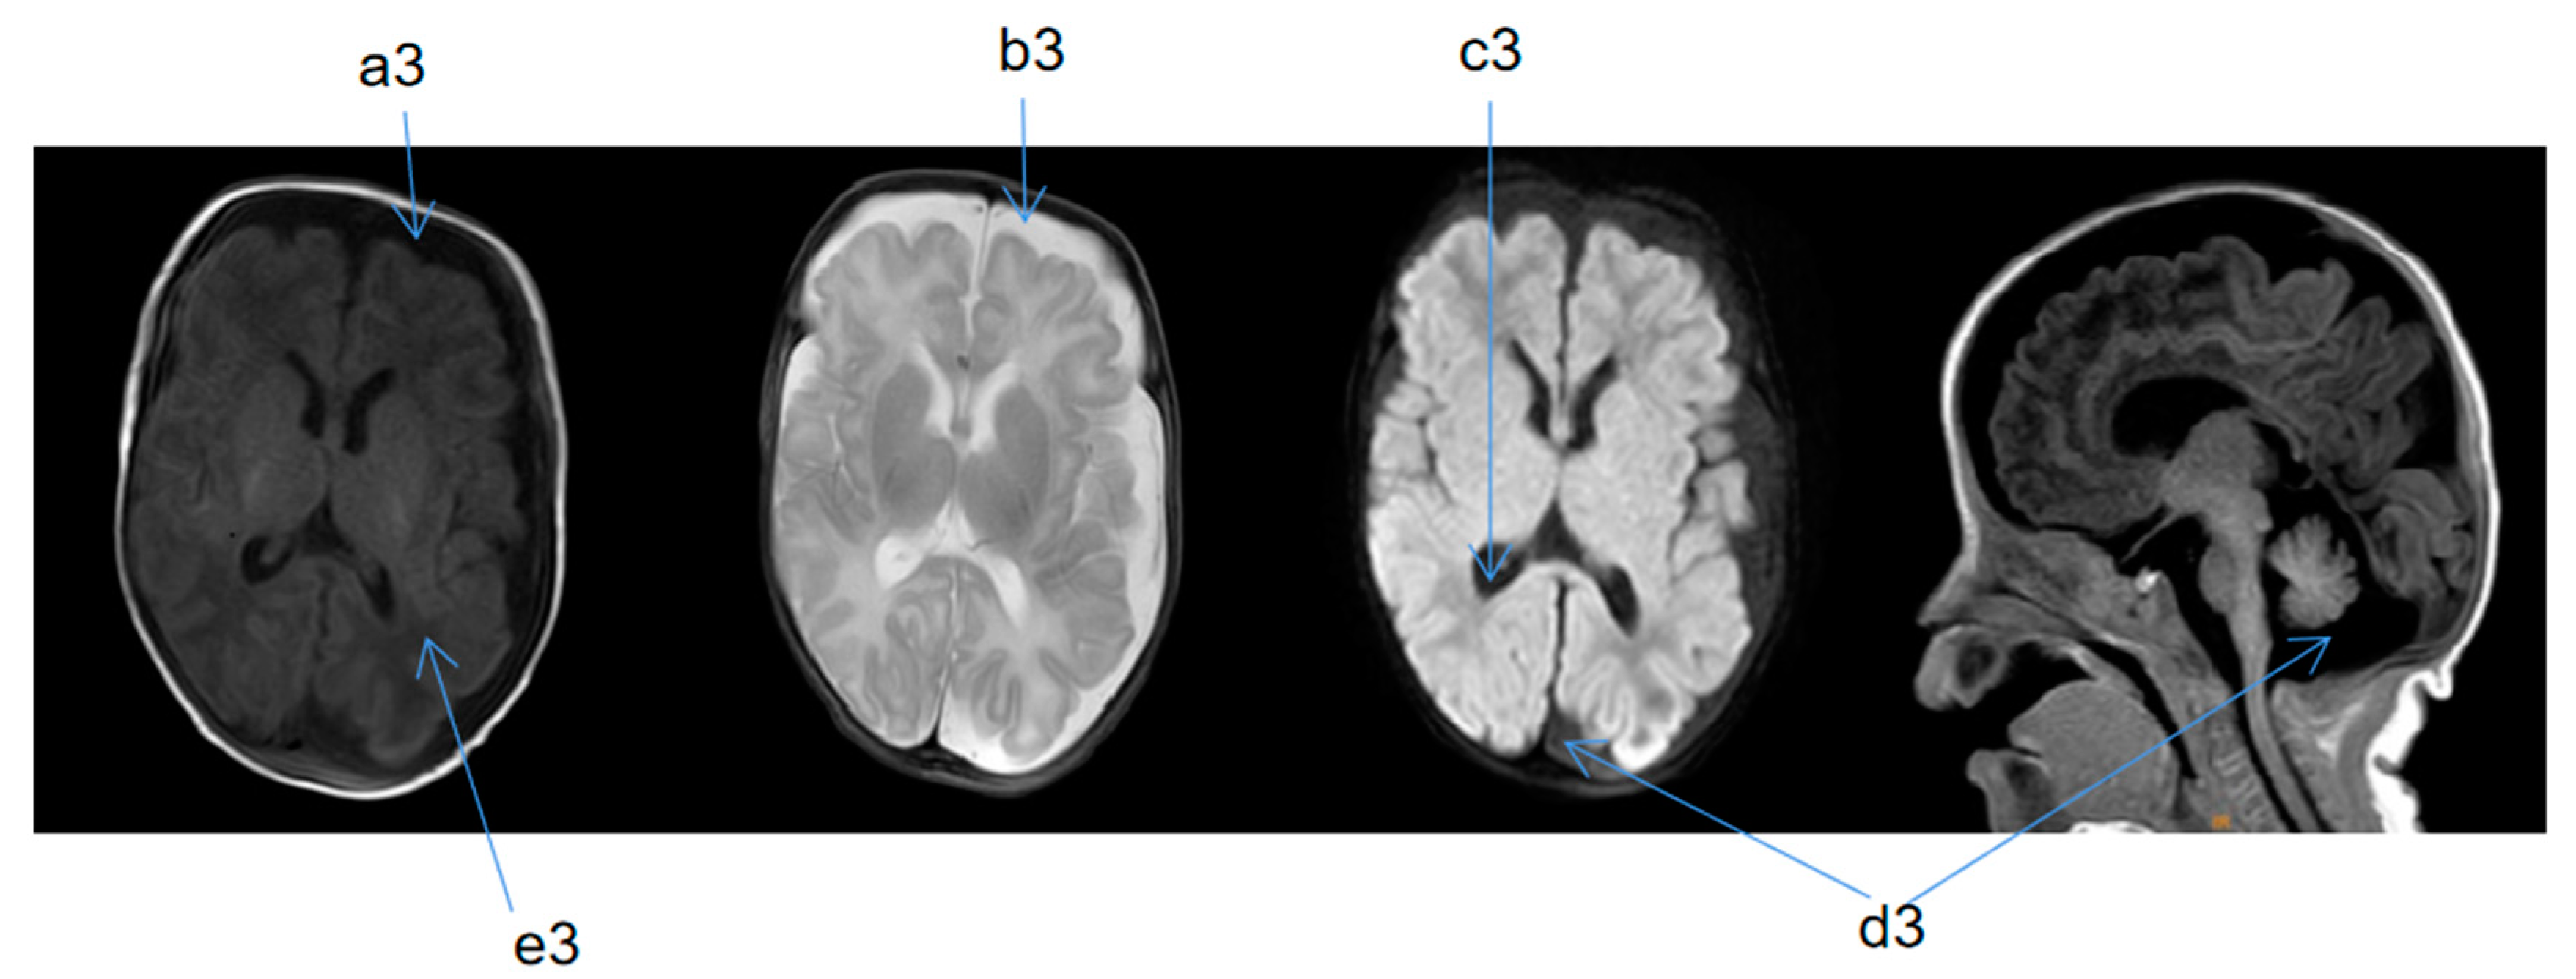

2.2. Supplementary Examination

| Cranial MRI abnormalities | + | + | + | + | + |